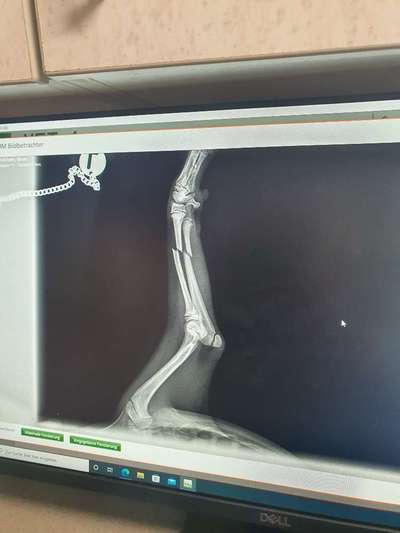

Update Mailo ist jetzt zuhause und es geht ihm ganz gut. Er macht das ganz toll und hat scheinbar keine Schmerzen, was das ruhig halten schwer macht. Aber wir sind konsequent...vielen Dank für die lieben netten Antworten...es hat mir definitiv geholfen. Es ist toll das es so ein Forum gibt.... Liebe Grüße Hallo... Ich habe eine Frage. Hat jemand Erfahrungen mit einem Beinbruch bei einem Welpen? Unser Mailo 16 Wochen alt, hat sich gestern Abend Elle und Speiche gebrochen 😭😭 er ist unglücklich gestürzt....und ich habe immer sooo aufgepasst und alles Welpensicher gemacht aber 1 Sekunde hat gereicht. Er hat jetzt heute morgen eine Platte bekommen...ich wäre dankbar wenn jemand Erfahrung hätte und mir was über die Heilung usw aus Erfahrung berichten kann und vielleicht auch was es so ca gekostet hat. Er soll jetzt noch einige Tage dort bleiben und ich habe Angst das er vielleicht den Bezug zu uns verliert. Er lebt erst 4 Wochen bei uns....danke schonmal.